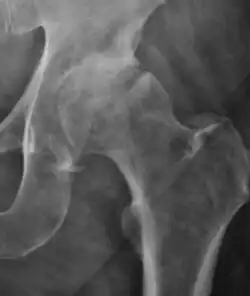

Plain radiography allows us to categorize the hip as normal or dysplastic or with impingement signs (pincer, cam, or a combination of both). Besides these, pathologic processes like osteoarthritis, inflammatory diseases, infection, or tumors can also be identified (Figure 1).[1]

Figure 1.

In adults, one of the main indications for radiographs is the detection of osteoarthritic changes (Figure 1(e)). Nevertheless, radiographs usually detect advanced osteoarthritis that can be graded according to the Tönnis classifications. The grading system ranges from 0 to 3, where 0 shows no sign of osteoarthritis. Intermediate grade 1 shows mild sclerosis of the head and acetabulum, slight joint space narrowing, and marginal osteophyte lipping. Grade 2 presents with small cysts in the femoral head or acetabulum, moderate joint space narrowing, and moderate loss of sphericity of the femoral head. Grade 3 is the severest form of osteoarthritis, which manifests as severe narrowing of the joint space, large subchondral cyst with productive bone changes that may lead to deformity of the bone components of the joint, while secondary osteoarthritis due to calcium pyrophosphate deposition can be diagnosed when calcification of hyaline cartilage and fibrocartilage is detected.[1]

There are other pathological conditions that can affect the hip joint and radiographs help to make the appropriate diagnosis. Acute bacterial septic arthritis can be diagnosed by radiographs when a fast regional osteoporosis and destructive monoarticular process develops (Figure 1(f)). In case of tuberculous or brucella arthritis it is manifested as a slow progressive process, and diagnosis may be delayed.[1]